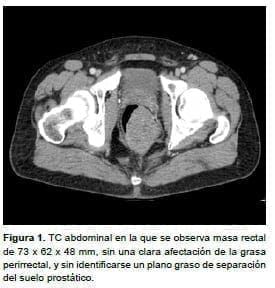

Ante estos hallazgos, se practicó una tomografía computadorizada (TC) abdominal en la que se observó una masa rectal de 73 x 62 x 48 mm (figura 1), sin demostrar una clara afectación de la grasa perirrectal, y sin que se identificara un plano graso de separación del suelo prostático. No se observaron ganglios linfáticos sospechosos.